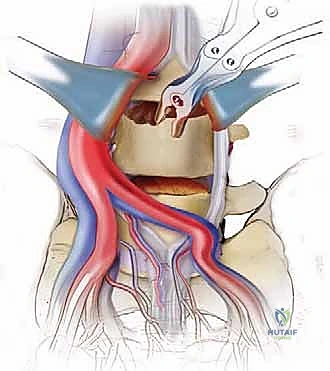

الخطوة 1: الشق الجراحي والوصول

يقوم الجراح بإجراء شق صغير (عادة من 3 إلى 5 بوصات) في أسفل البطن. يتم إزاحة عضلات البطن بلطف جانباً دون قطعها (في الغالب).

الخطوة 2: التعامل مع الأوعية الدموية (Vascular Mobilization)

هذه هي الخطوة الأكثر دقة. أمام العمود الفقري القطني توجد الأوعية الدموية الكبرى في الجسم (الشريان الأورطي والوريد الأجوف السفلي وتفرعاتهما). باستخدام أدوات دقيقة ورؤية مكبرة، يتم تحريك هذه الأوعية بلطف شديد لحمايتها وكشف القرص الفقري المستهدف (غالباً L4-L5 أو L5-S1).

الخطوة 3: استئصال القرص (Discectomy)

بمجرد كشف القرص، يقوم الأستاذ الدكتور محمد هطيف بإزالة المادة الغضروفية التالفة بالكامل. يتم تنظيف الصفائح النهائية للفقرات (Endplates) العلوية والسفلية بعناية فائقة للوصول إلى العظم النازف، وهي خطوة حاسمة لضمان نمو العظم الجديد والتحامه.

الخطوة 4: التحضير وزراعة القفص (Implant Insertion)

يتم قياس الفراغ المتبقي بدقة لاختيار الحجم المثالي للقفص الجراحي (Cage). يُصنع هذا القفص عادة من مادة PEEK أو التيتانيوم، ويتم حشوه بمادة عظمية (طعم عظمي ذاتي من المريض، أو طعم صناعي، أو بروتينات محفزة لنمو العظم BMP). يتم إدخال القفص بقوة في الفراغ، مما يؤدي فوراً إلى استعادة ارتفاع القرص الطبيعي وتوسيع المخارج العصبية (تخفيف الضغط غير المباشر).

الخطوة 5: التثبيت (Fixation)

لضمان أقصى درجات الثبات والسماح للعظم بالاندماج بمرور الوقت، يتم تثبيت القفص باستخدام شريحة معدنية صغيرة ومسامير من التيتانيوم تُثبت في الأجسام الفقرية من الأمام. في بعض الحالات، قد يرى الدكتور هطيف ضرورة إضافة تثبيت خلفي بمسامير عبر الجلد (Percutaneous Pedicle Screws) لزيادة الدعم.